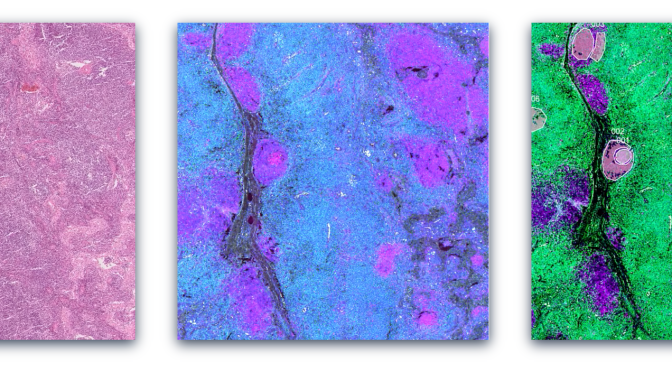

Most of the Science Scribbler projects launched so far have focused on 3D biological imaging data. When we ask questions about a particular sub-cellular structure or disease, we usually have to go through a process called segmentation: essentially colouring in every pixel that we count as being part of a particular class or label. Automated segmentation methods are constantly improving, but most of the time they still require a lot of expert annotation to either train or finetune the segmentation model. Creating this annotation is a huge bottleneck in processing all the data we collect. As a consequence, we usually have to compromise in some way: looking at a smaller sample size or asking less complicated questions.

Where volunteers help us in our research is in providing the annotations we need to train or refine our segmentation models. Once we have segmentation models that are working well, we can start to ask the really interesting questions – like what differences can we see in the mitochondria of healthy or diseased placenta? And what does that mean for our understanding of that disease?